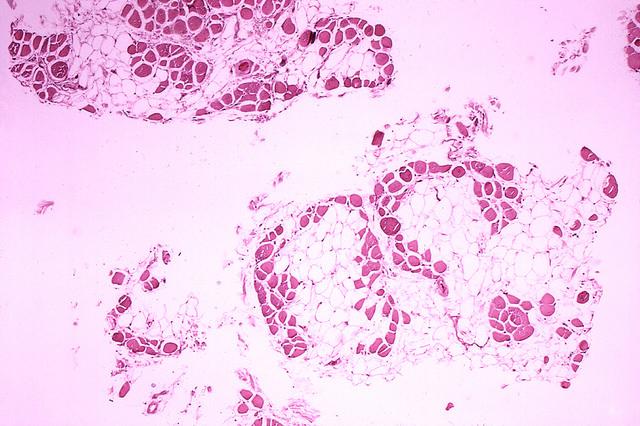

杜氏肌營(yíng)養(yǎng)不良癥患者的肌肉

Emma Kemp 使用Servier Medical Art制作的肌肉結(jié)構(gòu)主圖和說(shuō)明 iPS 細(xì)胞在肌營(yíng)養(yǎng)不良癥細(xì)胞療法研究中的應(yīng)用?。Edwin P. Ewing, Jr 博士拍攝的杜氏肌營(yíng)養(yǎng)不良癥患者的肌肉圖像,由美國(guó)衛(wèi)生與公眾服務(wù)部公共衛(wèi)生圖像庫(kù)提供?。Mike Kayser的肌纖維照片?,Wellcome Images。?